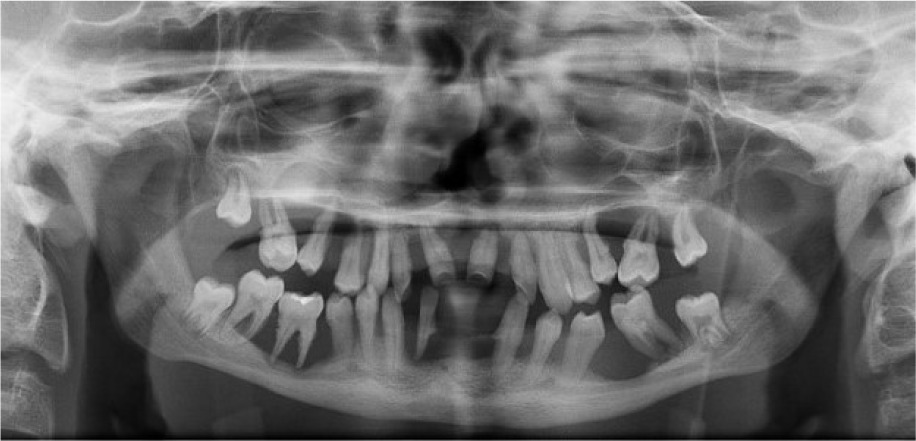

When the patient was 10, the exposure of two-thirds of palatal roots and third-degree loosening of teeth were observed (Fig. 3). A panoramic radiograph picture was taken (Fig. 4), which revealed complete absence of the bone base in all permanent first molars. Teeth 16 and 26 were qualified for extraction, which was performed in an outpatient setting under local anesthesia and antibiotic treatment (clindamycin, 10 mg/kg/dose). The obtained material from granulomatous lesions was submitted for histopathological examination, the results of which indicated non-specific inflammatory granulation tissue.